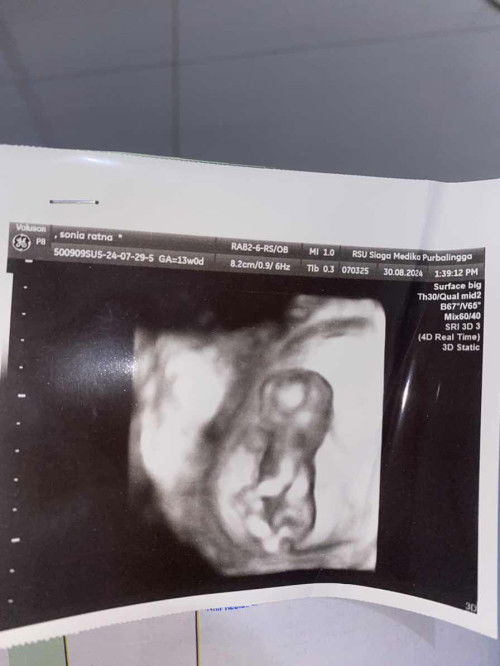

Hamil ke-2, usia 13w, didiagnosa Hydrops Fetalis (penumpukan cairan abnormal di beberapa bagian tubuh janin, lebih lengkapnya googling). Prognosisnya kurang bagus (bahkan lebih ke jelek), karena mengancam nyawa si janin. Sudah disarankan untuk tahap terminasi+kuret. Tapi Saya dan suami belum mau, karena masih ada DJJnya. Kami lebih memilih si janin bertahan sesuai kemampuannya, meskipun ujung2nya nggak bisa diselamatkan. Tinggal nunggu waktu aja. Awalnya sakit, tapi sekarang lebih legowo dan bisa cerita disini. Apapun kondisi si adek janin, kami tetap menyanyanginya. #hydropsfetalis #hygromacolli